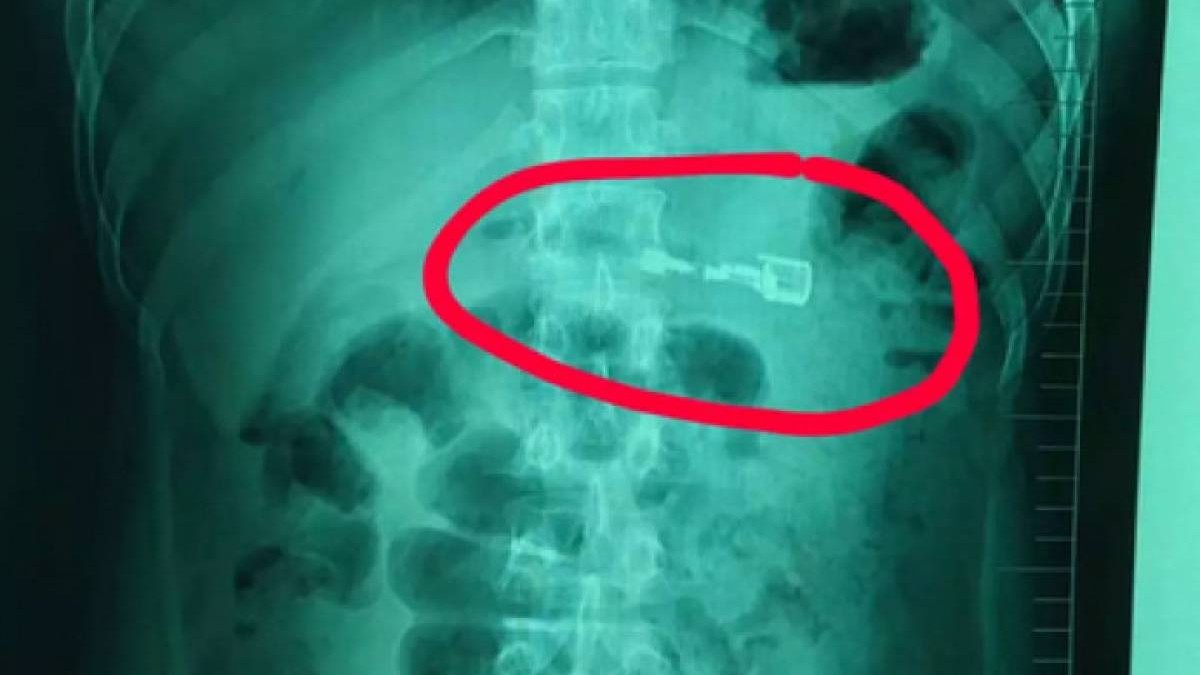

Қытайда дәрігерлер ер жігіттің асқазанынан газбен жанатын кәдімгі оттықты шығарып алды. Бұл туралы WeChat әлеуметтік желісіне 12 наурызда Ляонин провинциясындағы Шеньян қаласының ауруханасы өкілдері жеткізген, деп хабарлайды Zakon Lenta.ru-ға сілтеме жасап.

Жексенбіде, 10 наурыз күні таңертең бала жергілікті ауруханаға жеткізілді. Пациентке отау жасау тым қауіпті деп шешкен дәрігерлер Лиді Шэньян қаласындағы ірі ауруханаға жеткізді. Ол жерде пациенттің асқазан қышқылы сегіз сантиметрлік оттықтың пластигін еріте бастағаны анықталған. Оның ішіндегі газ кез-келген сәтте сыртқа шығып кетуі мүмкін екен.

Қауіпті зат Лидің асқазанында 30 сағаттай болған, ендігі алынбаса – жарылып кету қаупі болды. Дәрігерлер "зажигалканы" эндоскоптың көмегімен үш минуттың ішінде шығарып алды.